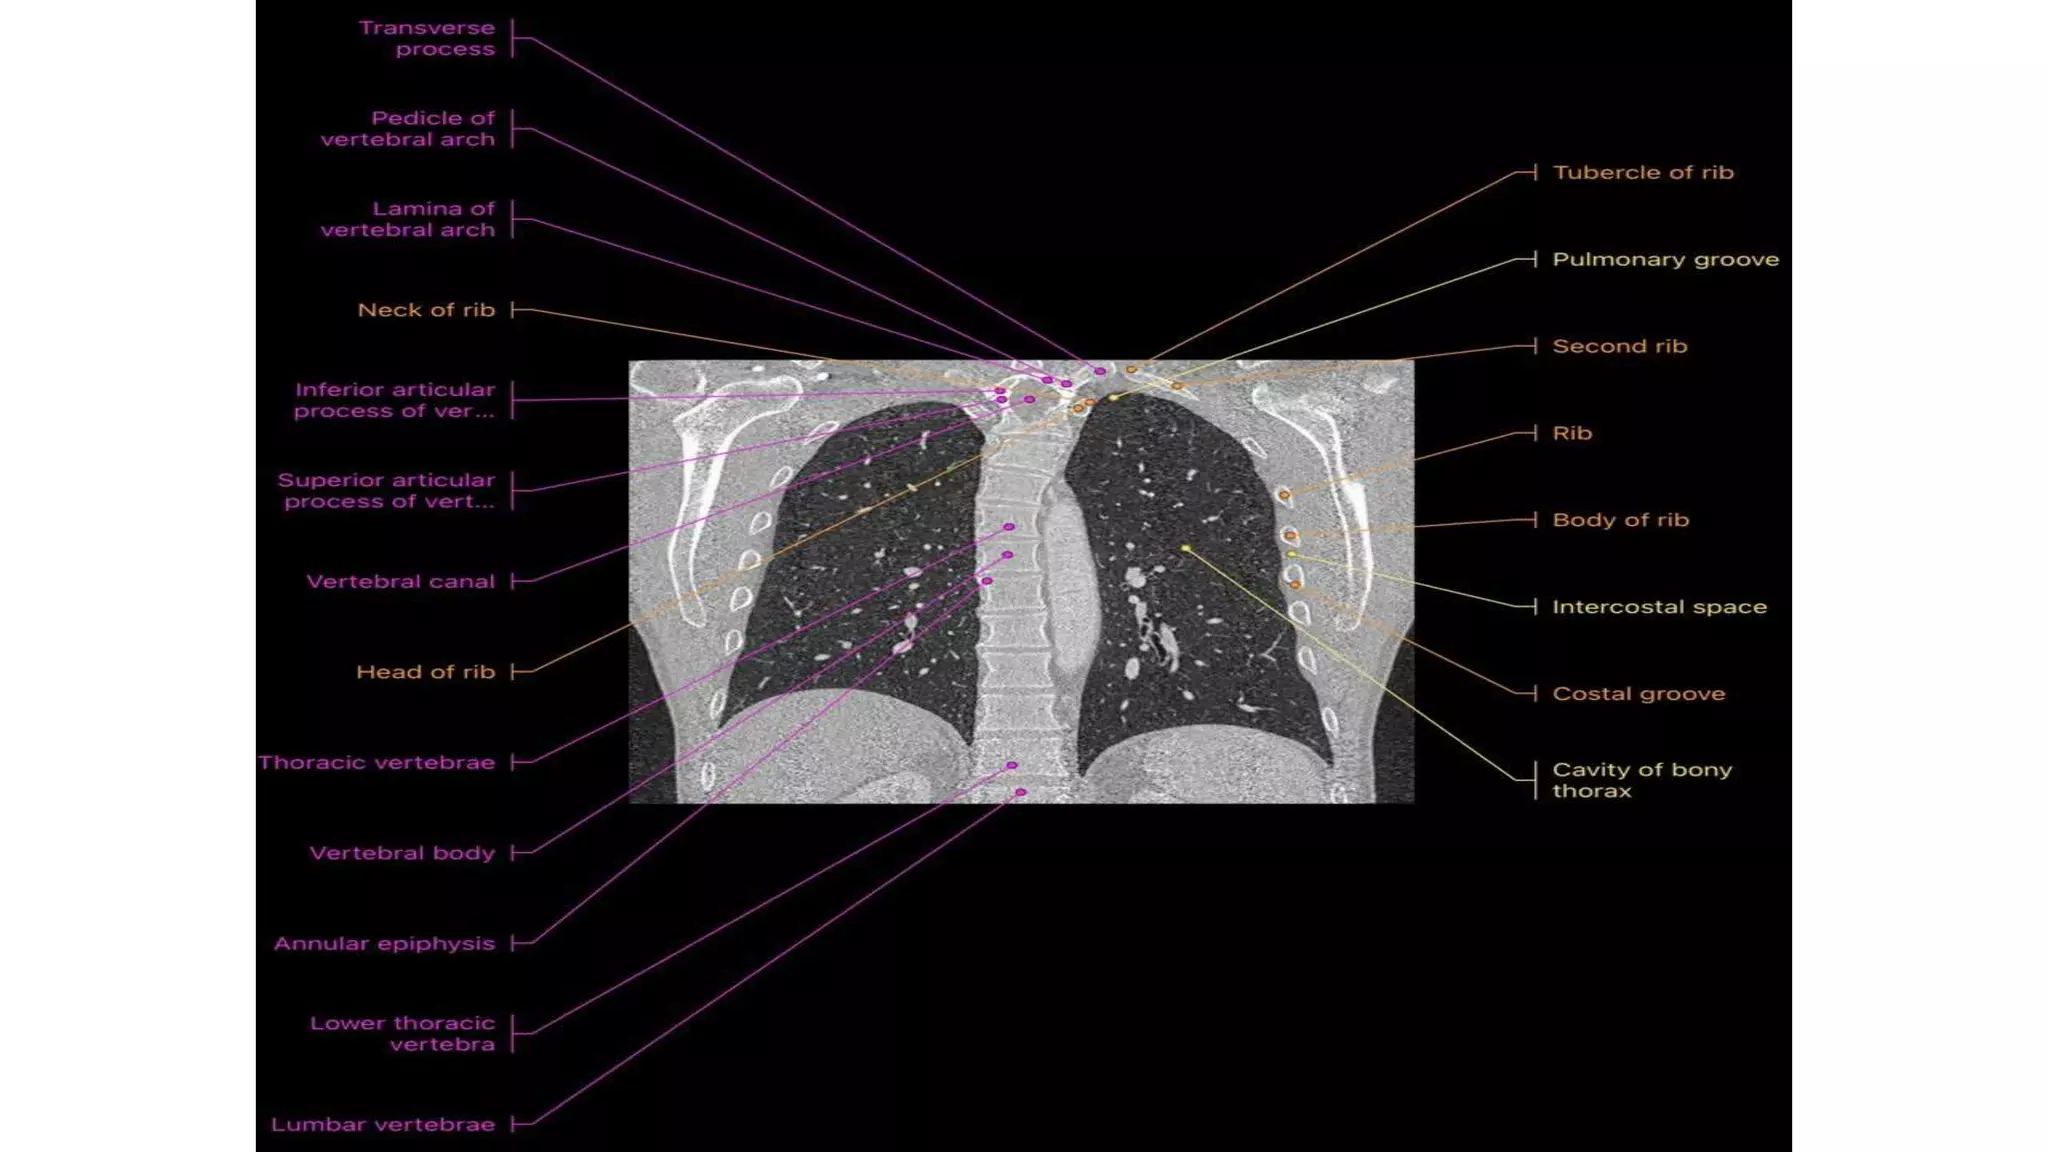

Thoracic spine

X-ray in AP and Lateral

projections.

Vertebral body (star ) of

T12 with rib hypoplasia;

T10–T11 intervertebral

foramina (circle ); T11

right pedicle(arrowhead )

Thoracic spine X-ray inAP and Lateral projections. Vertebral body (star ) of T12 with rib hypoplasia; T10–T11 intervertebral foramina (circle ); T11 right pedicle(arrowhead )